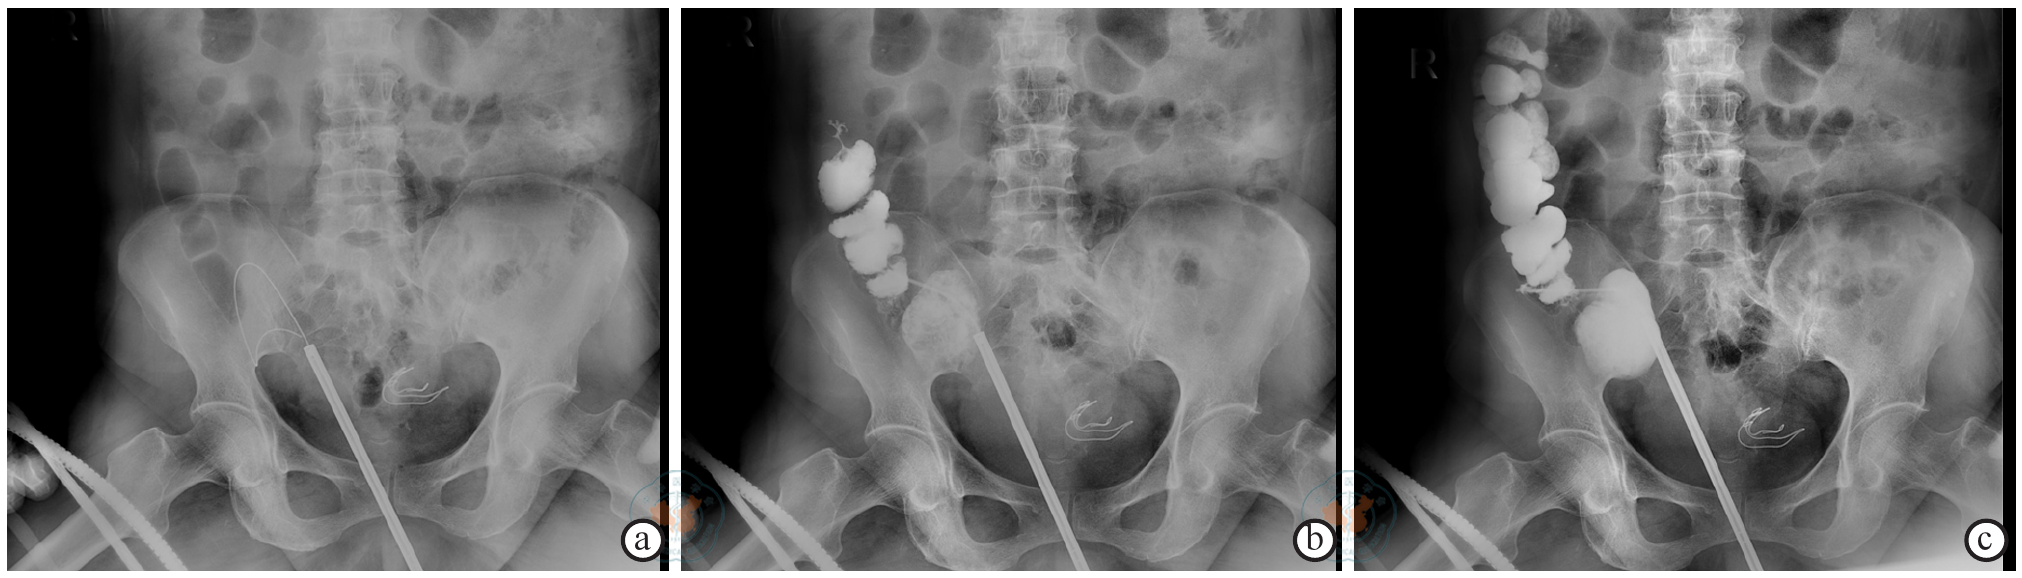

图3 盲肠膀胱瘘患者经尿道经膀胱瘘口插管术联合逆行膀胱造影注:a示经瘘口置入导丝20 cm,床旁摄片示导丝位于膀胱外,b~c示经导管注入碘帕醇后,回盲部和升结肠显影